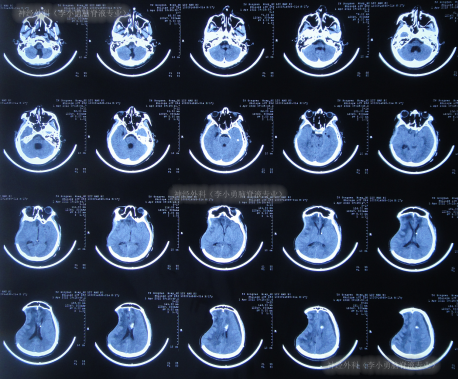

患者于2022年2月2日,不慎摔倒头部磕到地面,当时呈嗜睡状态,呕吐1次,大小便失禁,由120急送至当地县某医院,查头颅CT示右额部血肿(片子丢失),当即转至上级的河北省唐山市某医院,查头颅CT示右额部血肿、脑疝(图-1);检查期间出现昏迷、呕吐、四肢强直。

图-1:2022年2月2日头颅CT